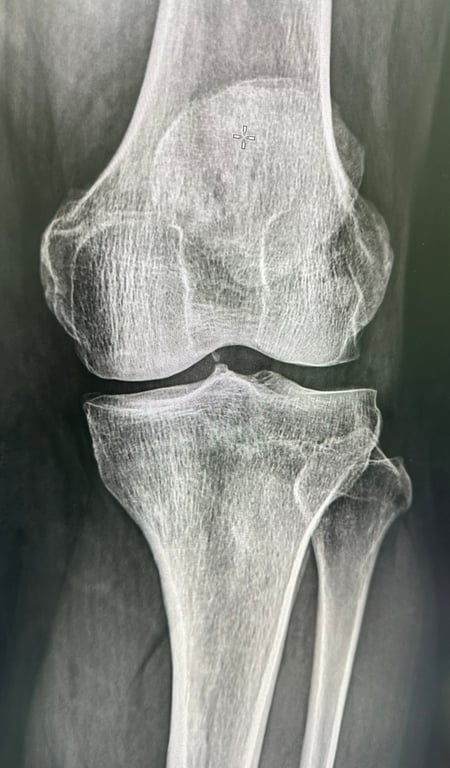

X光影像

醫師會透過詳細的病史詢問、膝關節的理學檢查(觸診、活動度測試)來初步評估。X光檢查是診斷退化性膝關節炎最主要的影像工具,可以清楚看到關節間隙變窄、骨刺形成、軟骨下骨硬化等退化徵象。